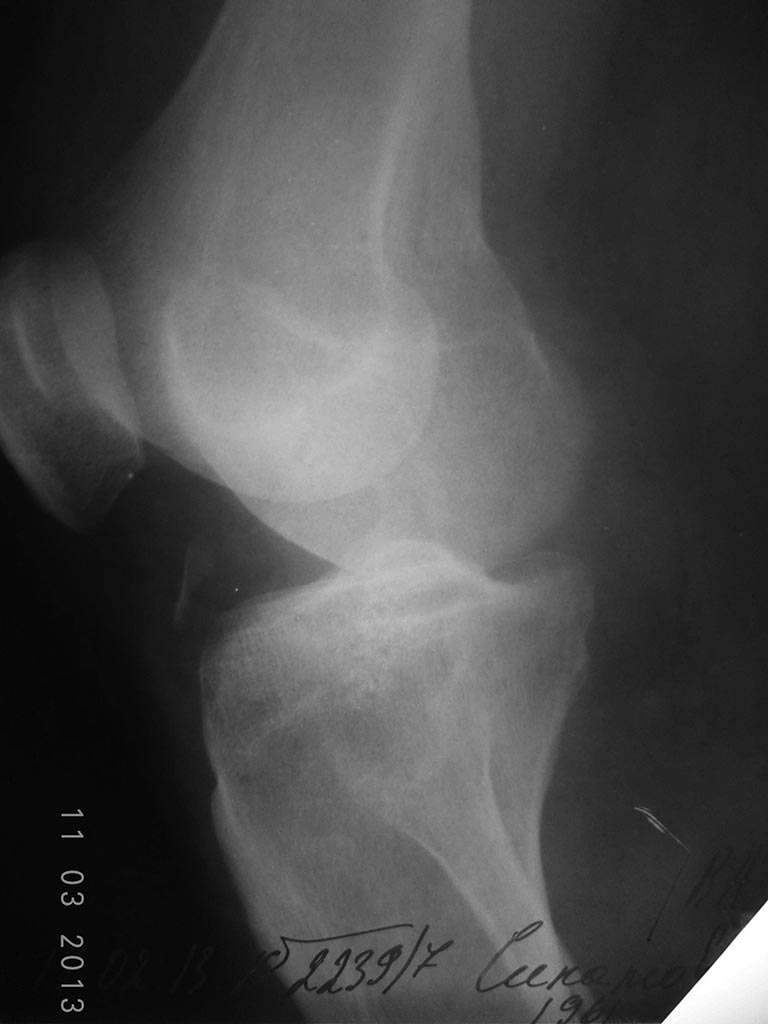

[Ortho] Перелом головки малоберцовой кости.

Боковая проекция Вашему вниманию.